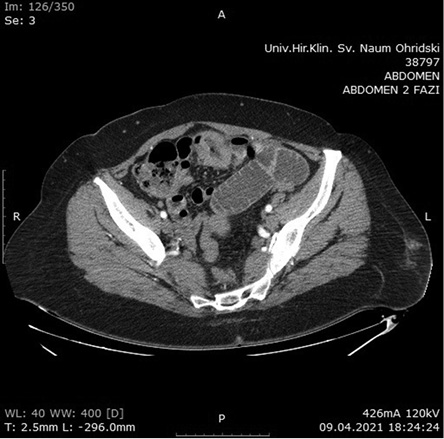

The macroscopic histopathology analysis revealed the presence of a tumor with dimensions of 6x5x2.5 cm (ulcerative type) that spreads in the surrounding adipose tissue. The microscopic aspect of hematoxylin and eosin staining presented with infiltrative growth of lymphoid cells with large nuclei and frequent mitoses. Immunohistochemical staining showed high proliferation over 90% of Ki67 and CD20 (Figures 3a, 3b, and 3c). The overall pathology report concluded the presence of aggressive diffuse large B-cell lymphoma.

3a

3b

3c

Figure 3. 3a – Hematoxylin Eosin stain with infiltrative growth of Lymphocytes, 3b – Ki67 stain with high proliferation, 3c – CD20 stain with proliferation over 90% (100x magnification)